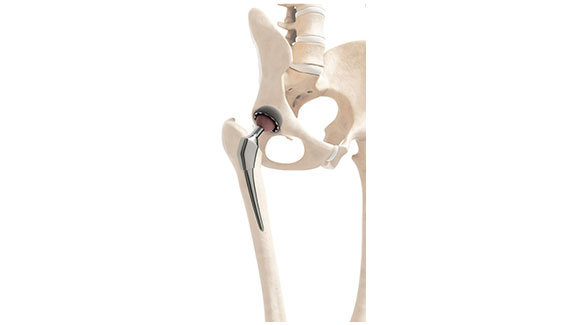

人工関節置換術(股)

人工股関節手術とは

股関節は大腿骨の丸い骨頭部分が骨盤側の関節面に組み合わさって、関節軟骨により表面はおおわれています。

それにより滑らかな股関節の動きができる仕組みとなっています。変形性股関節症では、関節軟骨が変性し摩耗を起こしています。

その結果股関節に体重をかける度に痛みを伴うようになってしまい、この関節面がひどく摩耗してしまった場合です。保存加療が限界である場合、年齢によりますが多くは人工股関節手術を選択していきます。

人工股関節置換術は、摩耗・損傷した股関節の骨頭と骨盤側の関節面をインプラントに置き換える手術で、主にステム、骨頭、カップで構成されます。インサートにはポリエチレンが多用されます。

麻酔は施設により異なりますが、一般的に全身麻酔で行われ、手術時間は1~2時間程度です。

術式には、簡単に言えば後方(お尻付近)と前方(鼠径部付近)やその中間からのアプローチがあり、医師の技量や慣れた方法によって選択されます。手術では、骨頭を切除し、骨盤側の関節面を整えた後、適合するカップを設置します。さらに、大腿骨にステムを挿入し、骨頭とカップインサートを連結して股関節を整復します。

術後は通常2週間程度で退院可能です。

また、レントゲンの見た目が似ている手術に、人工骨頭挿入術があります。違いは骨盤側の関節面も取り替えるのが人工股関節手術です。